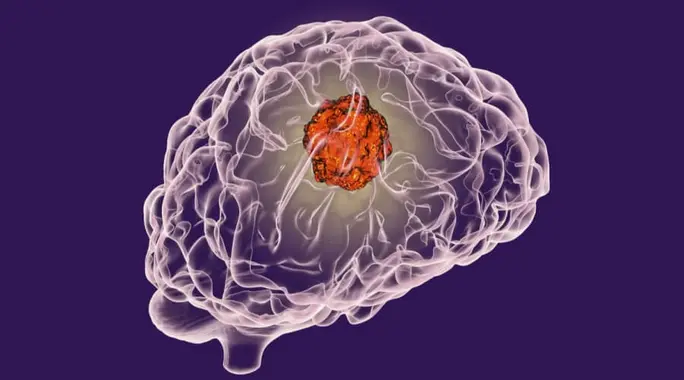

غالبًا ما يرتبط الحديث عن أورام المخ بالجراحة كحل أساسي. ولكن ماذا لو كانت هناك طرق فعالة لعلاج أورام المخ دون الحاجة إلى تدخل جراحي؟ في الواقع، شهد الطب تطورات كبيرة سمحت بظهور خيارات علاجية غير جراحية يمكن أن تحدث فرقًا حقيقيًا في حياة المرضى، خاصةً عندما تكون الجراحة محفوفة بالمخاطر أو غير ممكنة. استكشف معنا كيف يمكن تحقيق علاج أورام المخ بدون جراحة، وما هي أبرز هذه الأساليب المبتكرة.

نعم، من الممكن تمامًا علاج أورام المخ أو السيطرة عليها بفعالية دون الحاجة إلى جراحة. يعتمد قرار العلاج غير الجراحي على عدة عوامل رئيسية، بما في ذلك موقع الورم، وحجمه، ونوعه، وصحة المريض العامة، ومدى تأثيره على وظائف الدماغ الحيوية. في بعض الحالات، قد تكون إزالة الورم جراحيًا محفوفة بمخاطر عالية، مما يجعل الخيارات غير الجراحية هي الأفضل.

تساهم هذه العلاجات في تقليل حجم الورم، تخفيف الأعراض، وتحسين جودة حياة المريض بشكل ملحوظ. لنستعرض أبرز هذه التقنيات المتوفرة اليوم.